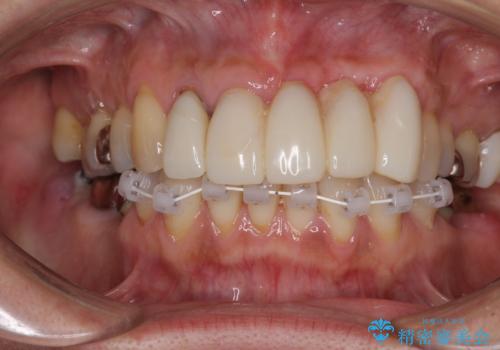

- 前歯の歯肉の腫れを気にして来院された患者様です。

前歯のみならず、奥歯の銀歯や下顎前歯のデコボコなど、色々と気になる部分を治したいとのことでした。

前歯は抜歯が必要であったので、抜歯を行い、その後歯肉移植をおこなった上でオールセラミックブリッジによる補綴治療を行うこととしました。

下顎と上顎臼歯部については矯正治療を行い、奥歯の欠損部位はオールセラミックブリッジを、その他の銀歯はセラミックインレーなどにより治療を行うこととしました。